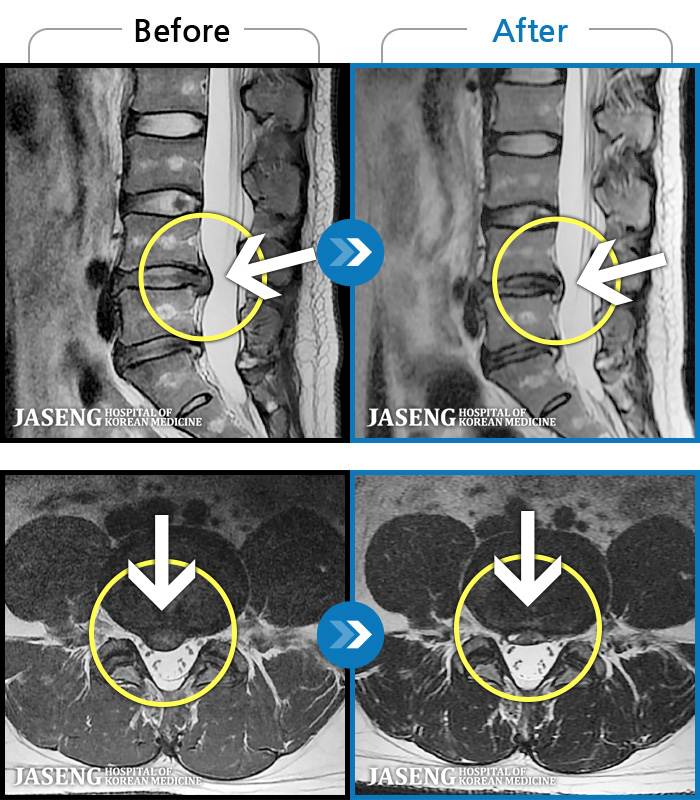

MRI 치료사례

허리디스크

안산 · 조창현 원장

심한 허리 통증으로 내원

촬영시기

2025.04.22 ~ 2025.11.03

허리 통증 및 오른쪽 다리로 내려가는 심한 통증으로 혼자 보행 어려워 응급 내원

2019.09.21 ~ 2021.10.05